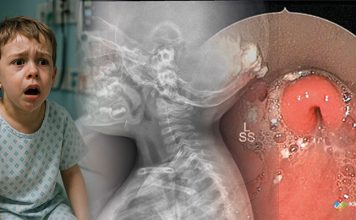

Pnömomediastinum

Pnömomediasten, mediastinal boşlukta hava bulunması ile karakterize nadir görülen ancak acil servislerde karşılaşılabilen önemli klinik durumlardan biridir. Travma, alveoler rüptür, astım atağı, yoğun öksürük,...